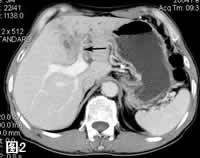

图2: 增强CT扫描门静脉期,示肿块门静脉期有轻度增强,左肝门静脉支受累狭窄(箭号)。